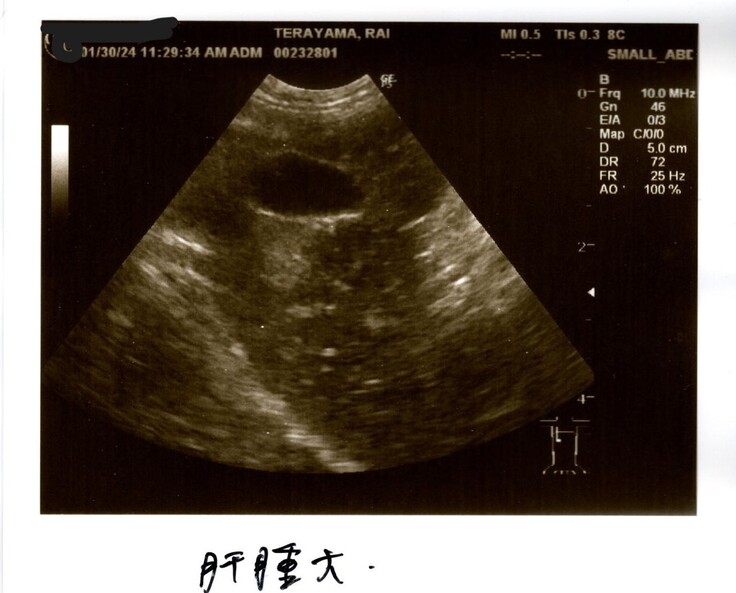

①肝腫大→肝臓が大きくなっている(炎症を起こしている)